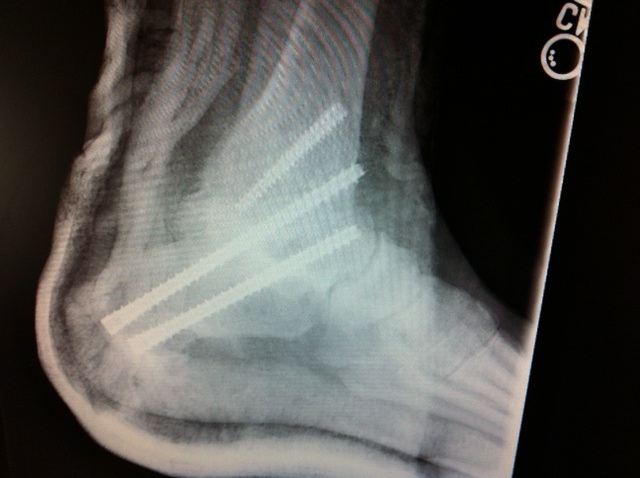

Boy you guys are making me feel BETTER. Old injury, original fusion 2003, sub-taler fusion 2012. 6 weeks non-weight bearing hence my wonderful wheel chair, ramp, etc. Child’s eye view of things…more on that soon, in the meantime I REALLY appreciate the good wishes. P.S. don’t climb trees to avoid studying!!! XO BH